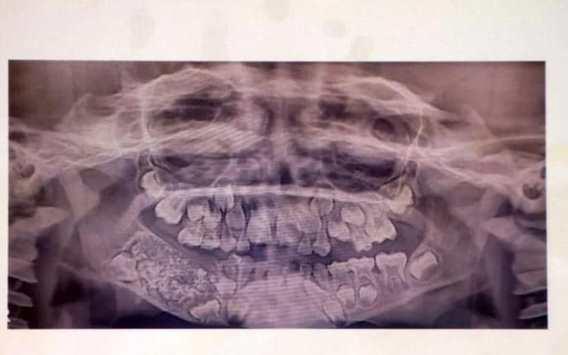

| اقتلاع 523 سنا من فم طفل بالهند |

أعلن أطباء في الهند، الأربعاء، اقتلاعهم لـ526 سنا وضرسا من فم طفل عمره 7 سنوات، يعاني من حالة طبية غير عادية.ويعاني الطفل من ورم في الجانب الأيمن من الفك السفلي له منذ أن... |